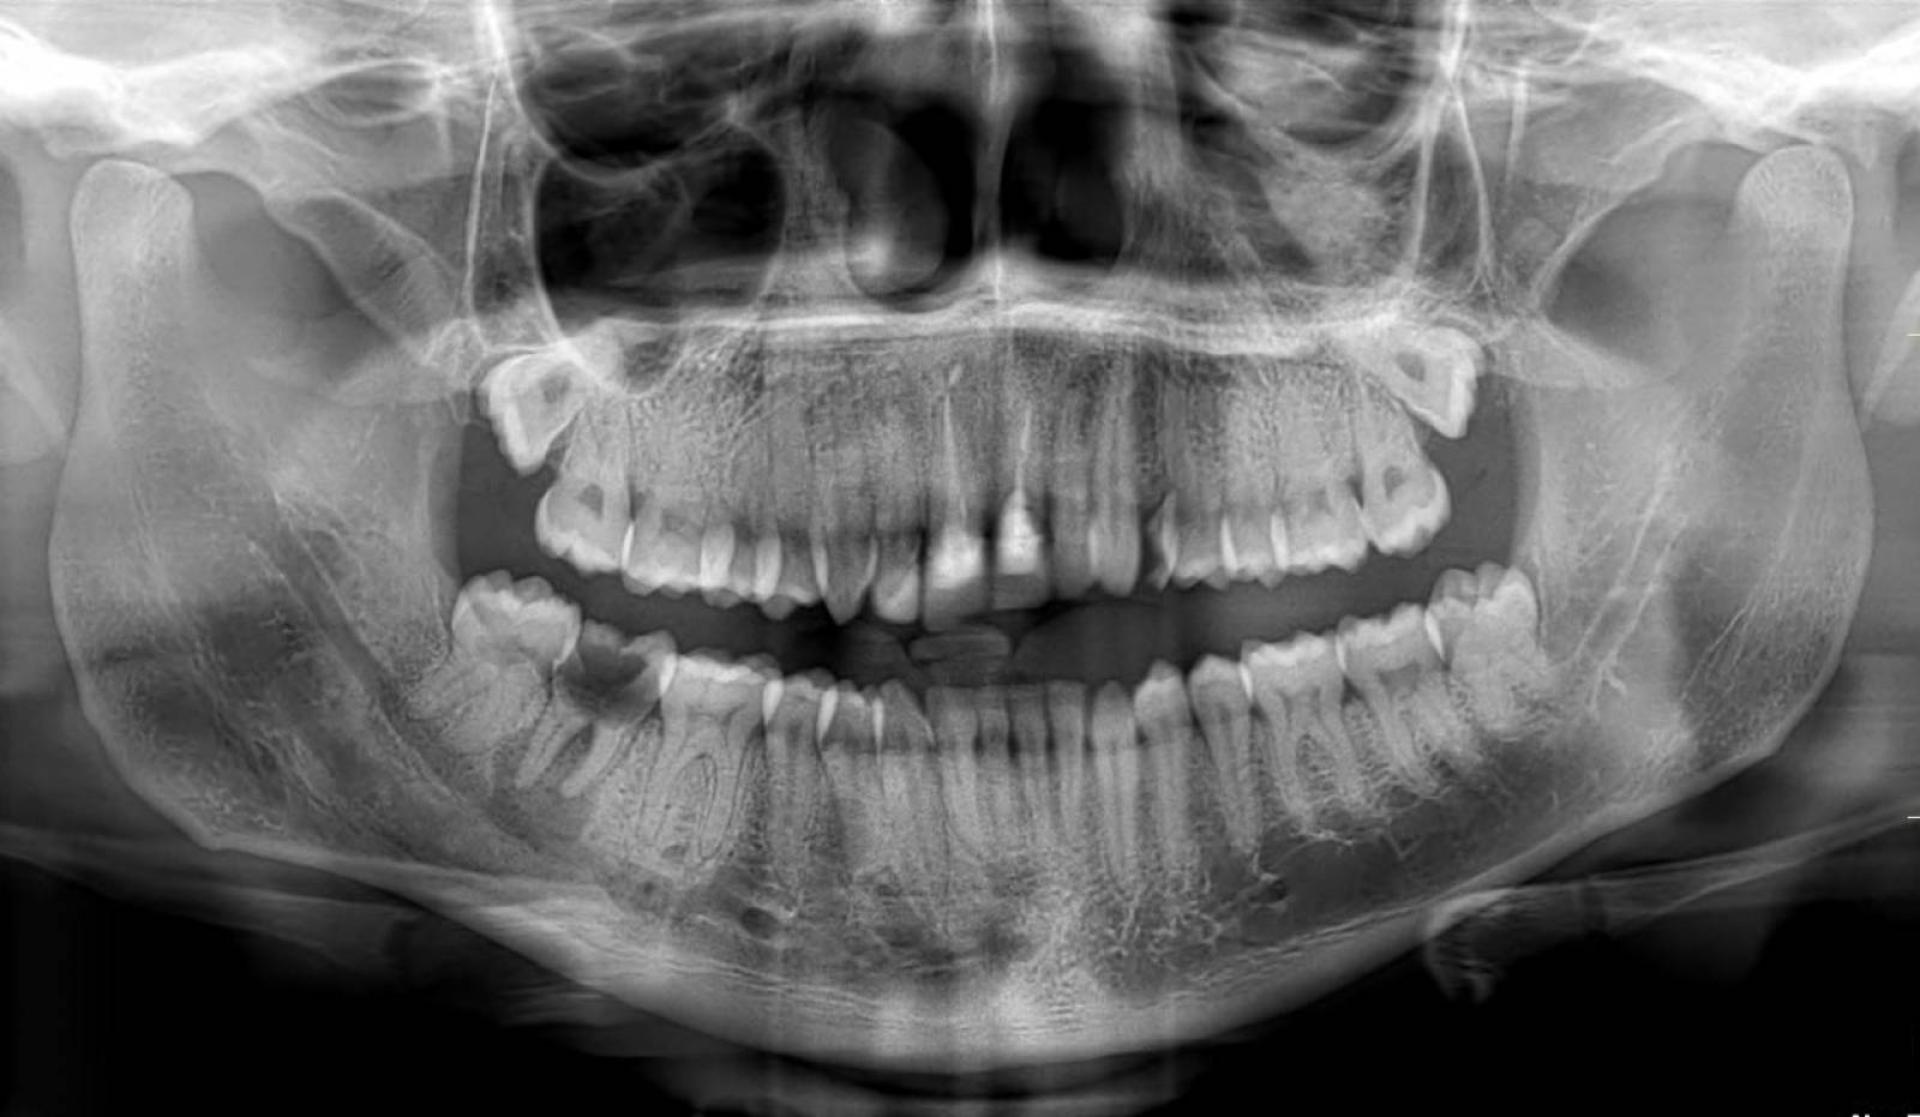

Imagerie panoramique dentaire avec détection précoce caries profondes et pathologies maxillaires à Auriol

L’imagerie panoramique dentaire joue un rôle primordial dans la détection précoce des caries profondes et des pathologies maxillaires, notamment à Auriol. Cet examen moderne permet de visualiser l’ensemble des structures buccales pour établir un diagnostic précis et guider le traitement adapté. I...

La radiographie panoramique dentaire permet de réaliser une imagerie de la totalité de la dentition ainsi que des mâchoires. Elle permet de connaître le positionnement des dents ainsi que les éventuelles anomalies au contact des racines et au niveau des couronnes. Elle permet de mettre en évid...